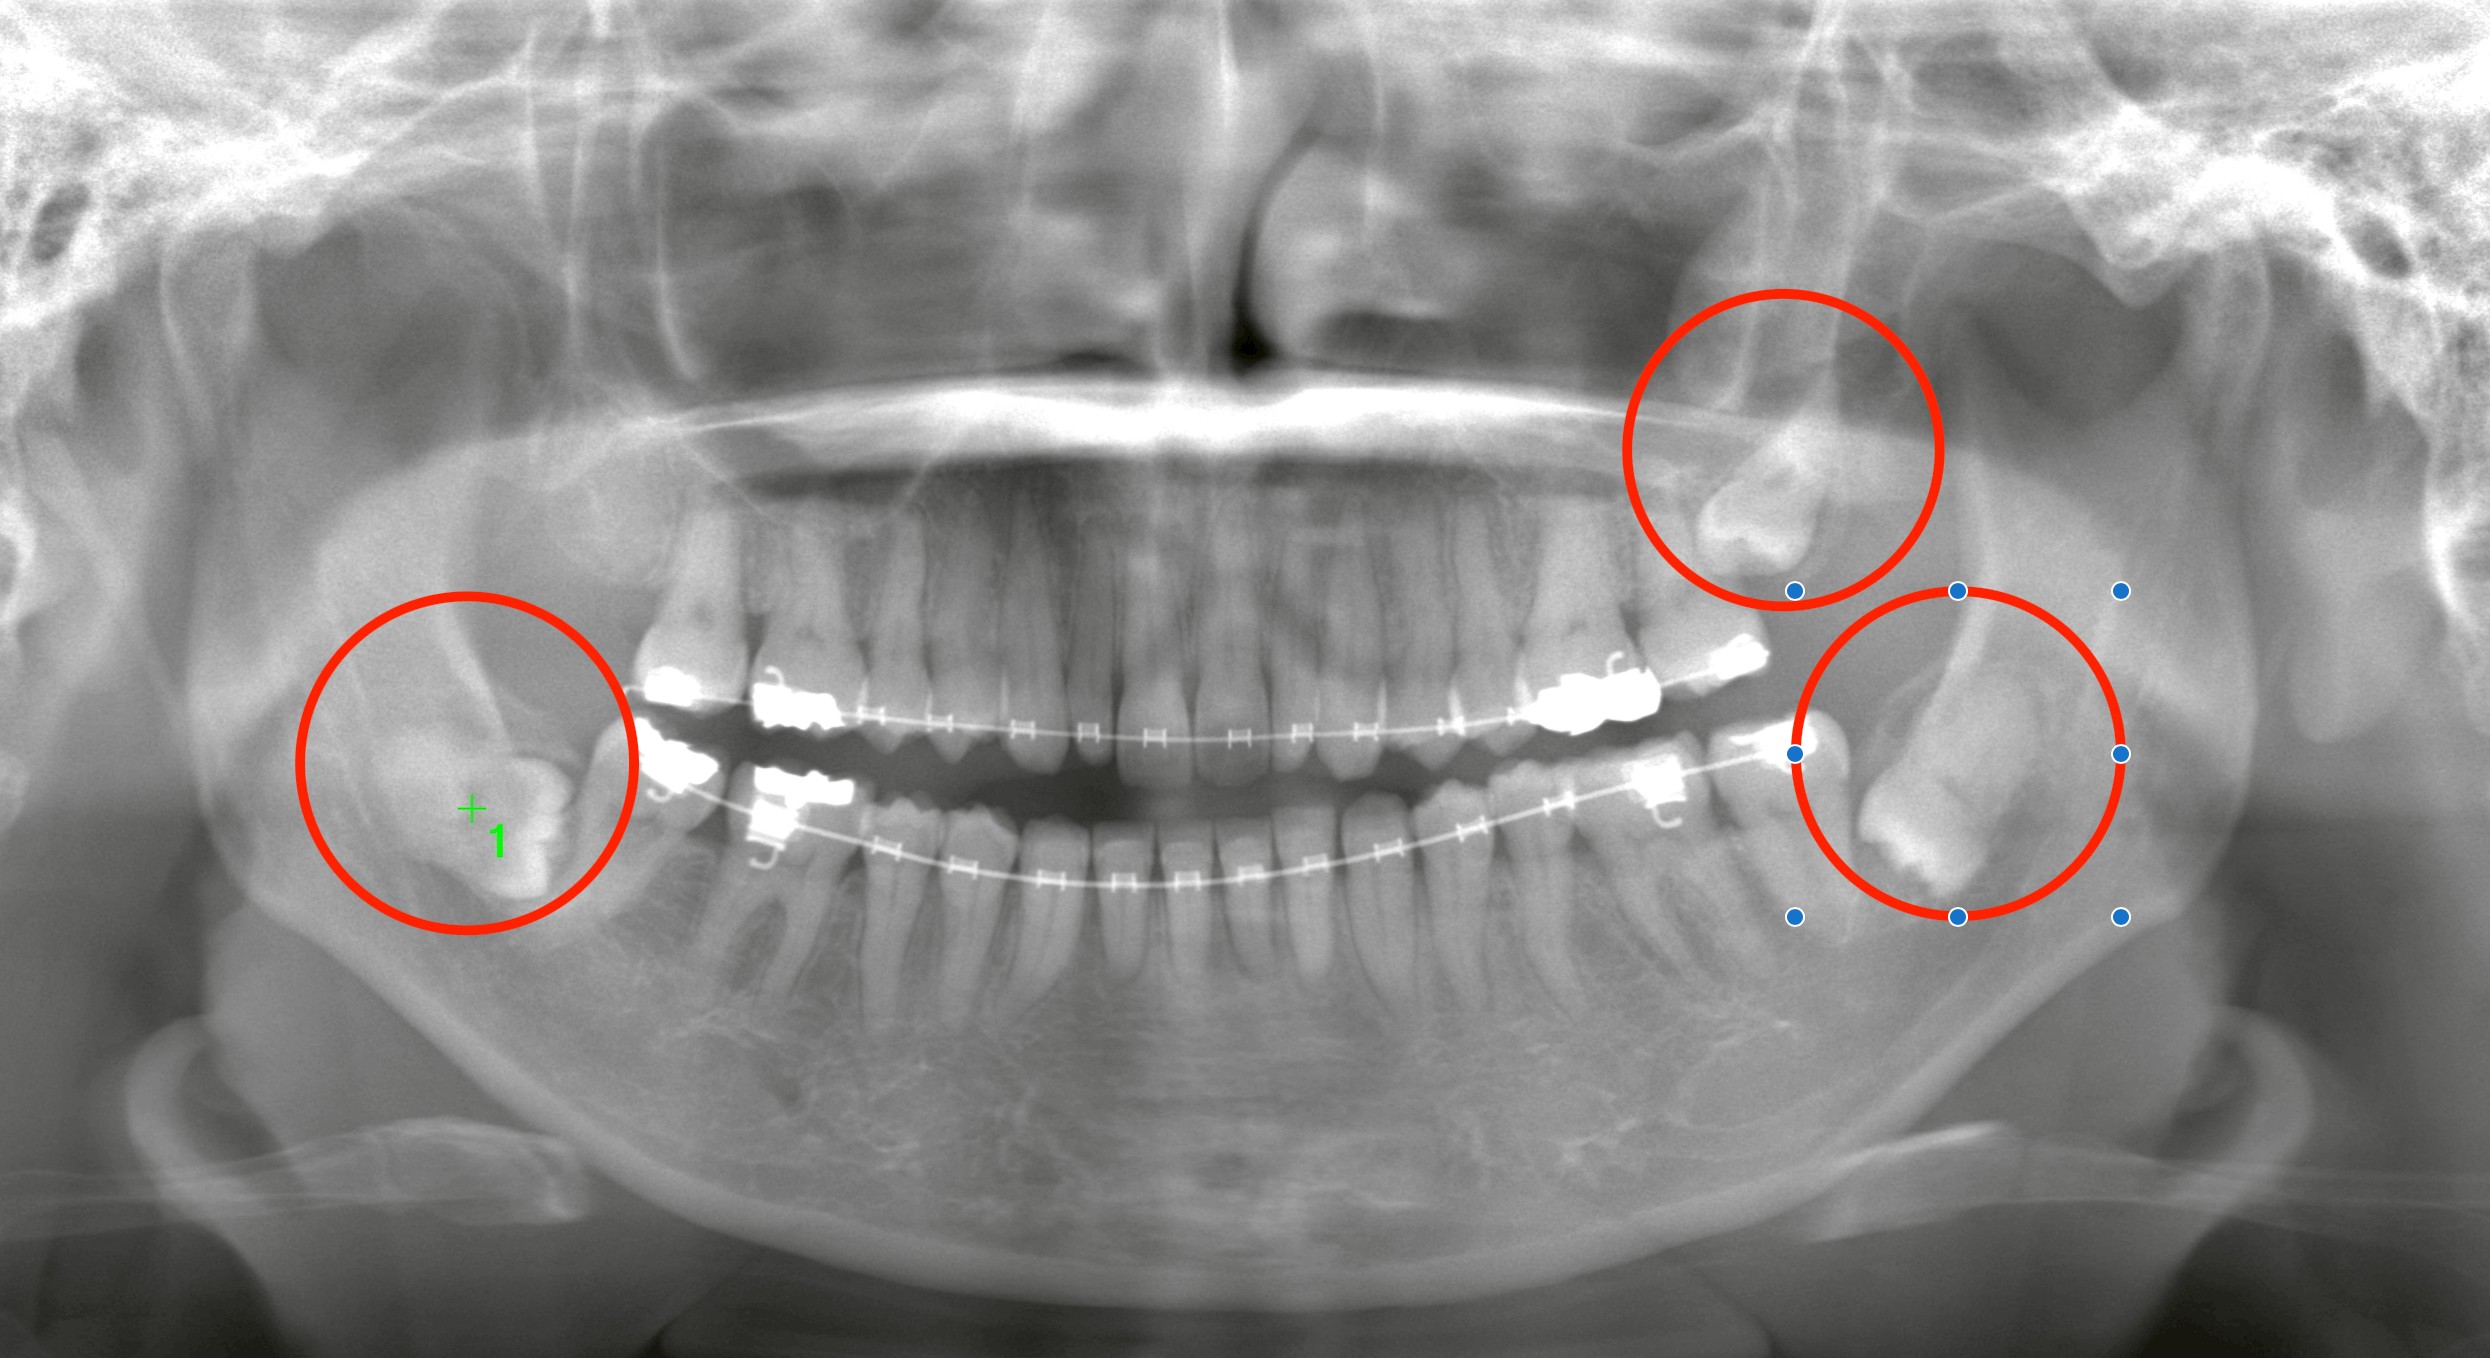

本日は、矯正治療中のアンギュレーション(歯軸改善)を妨げていた右下の埋伏親知らずの抜歯を行いました。

■ 右下の埋伏親知らずを抜歯

CTで確認すると、親知らずの一部が骨と癒着している状態。

長期間骨内に埋まっていた親知らずは、炎症がなくても骨とくっつくように“癒着”を起こすことがあります。

矯正の仕上げ段階で「動きが悪い」と感じるとき、埋伏親知らずが原因であるケースは少なくありません。

今回は、矯正治療の仕上げを妨げていた埋伏親知らずの抜歯を行いました。

癒着がある難易度の高いケースでしたが、的確な診断と精密な処置で安全に完了しました。